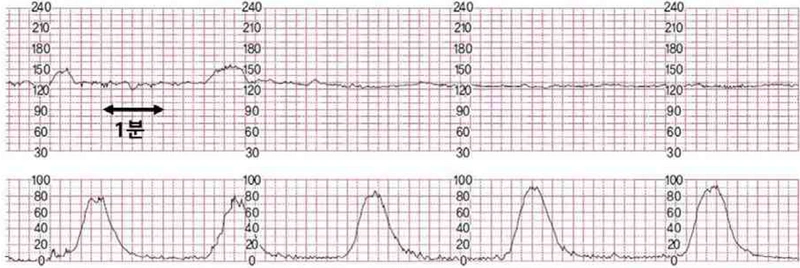

임신 39주 5일된 초산부가 양수가 터지고 진통이 시작되어 병원에 왔다. 혈압은 128/82 mmHg, 맥박은 78회/분, 체온은 37.0도이다. 니트라진 검사는 파란색이다. 초음파 검사상 태아는 두위, 예측 몸무게 3200g, 양수 지수는 9cm, 태반은 정상이다. 골반 검사상 자궁경부 7cm 확장되었고, 60% 소실되었으며, 태아 하강도는 -1 였다. 2시간 경과 후 골반 검사상 자궁경부 8cm 확장, 60% 소실, 태아 하강도는 0이다. 전자 태아 심박동-자궁수축감시검사 결과이다. 처치는?

• 산모의 니트라진 검사가 푸른색이라는 것은 양막파수가 있다는 것을 의미한다. 자궁 수축력은 200MVU이상으로 충분하다고 볼 수 있고, NST에서도 fetal distress는 없다.